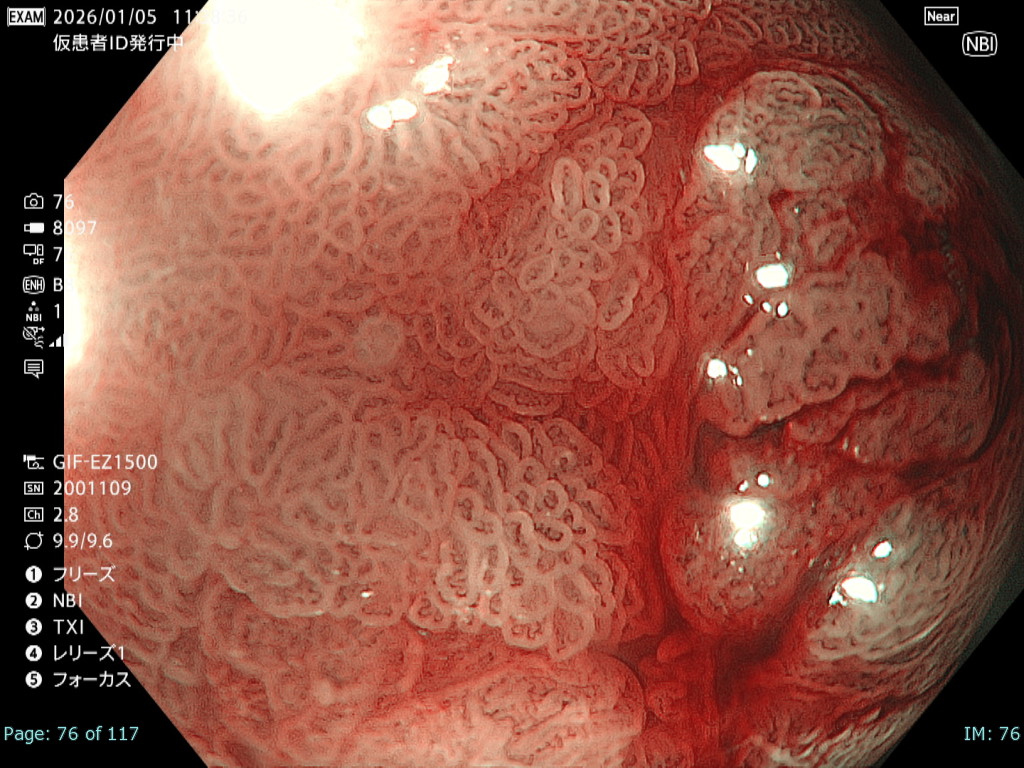

• NBI+TXI観察② (拡大)

切替前 NBI強調設定:B8

NBI+TXIレベル:中

図6

出血の影響を受ける条件下でも、NBI+TXI拡大観察は、NBI拡大観察と比較し、微小血管構築像がより明瞭になる印象だった。